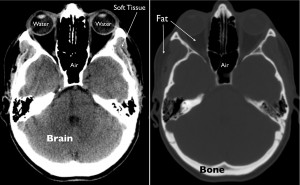

The primary physical quantity that is captured with CT is density, or mass per unit volume. Prior to display and storage of CT images, pixel intensities are mapped to a standard numerical scale to allow reliable discrimination between different densities of tissue such as air, water, fat, bone, and various brain constituents. When the images are reviewed on a computer, the intensities are further modified by a process referred to as windowing in order to optimally depict the density of different tissues for visual display. Extremely dense material, such as metal or bone, appears bright on CT images, whereas tissue that is less dense, like fat or water, appears dark.